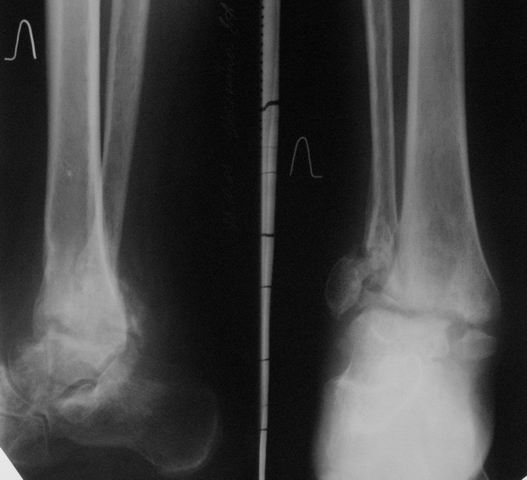

Уважаемые коллеги! Обратилась женщина 45 лет. Травма 2 года назад (март 2005 г.) - открытый 2-х лодыжечный перелом левой голени.

К сожалению, рентгенархив недоступен. Лечилась на вытяжении, затем гипсовой повязкой. Рана у внутренней лодыжки зажила вторичным натяжением. Сращения не наступило. В июне 2005 г. выполнялся артродез по Кэмпбеллу, фиксация в гипсовой повязке 3.5 мес. Сейчас нога полностью неопороспособна, выраженная патологическая подвижность. Признаков инфекции нет. Помогите определиться с методом артродеза, фиксации (КДО?), нужно ли вскрывать сустав, костная пластика? Пациентка, намучавшись за 2 года. "готова на любые эксперименты" (ее слова).Спасибо, с уважением, А. Минервин

Можно: 65-летняя пациентка, оперирована по поводу несросшегося в гипсе перелома лодыжек с патологической вальгусной установкой стопы и выраженным нарушением опрной функции. Оперирована через 6 месяцев после травмы. Рентгенограммы через 4 месяца после операции.